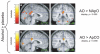

Results: Alcohol infusion enhanced the contrast between AO and NApO in the NAc, and in orbitofrontal, medial frontal, and precuneus/posterior cingulate regions. The contrast between AO and appetitive control odors (ApCO; chocolate and grape) was similarly larger in the orbital, medial frontal, precuneus, and posterior cingulate/retrosplenial areas, with the most robust finding being a potentiated response in the posterior cingulate/retrosplenial area. The orbital region is similar to an area previously shown to manifest satiety-related decreases in activity induced by food cues.